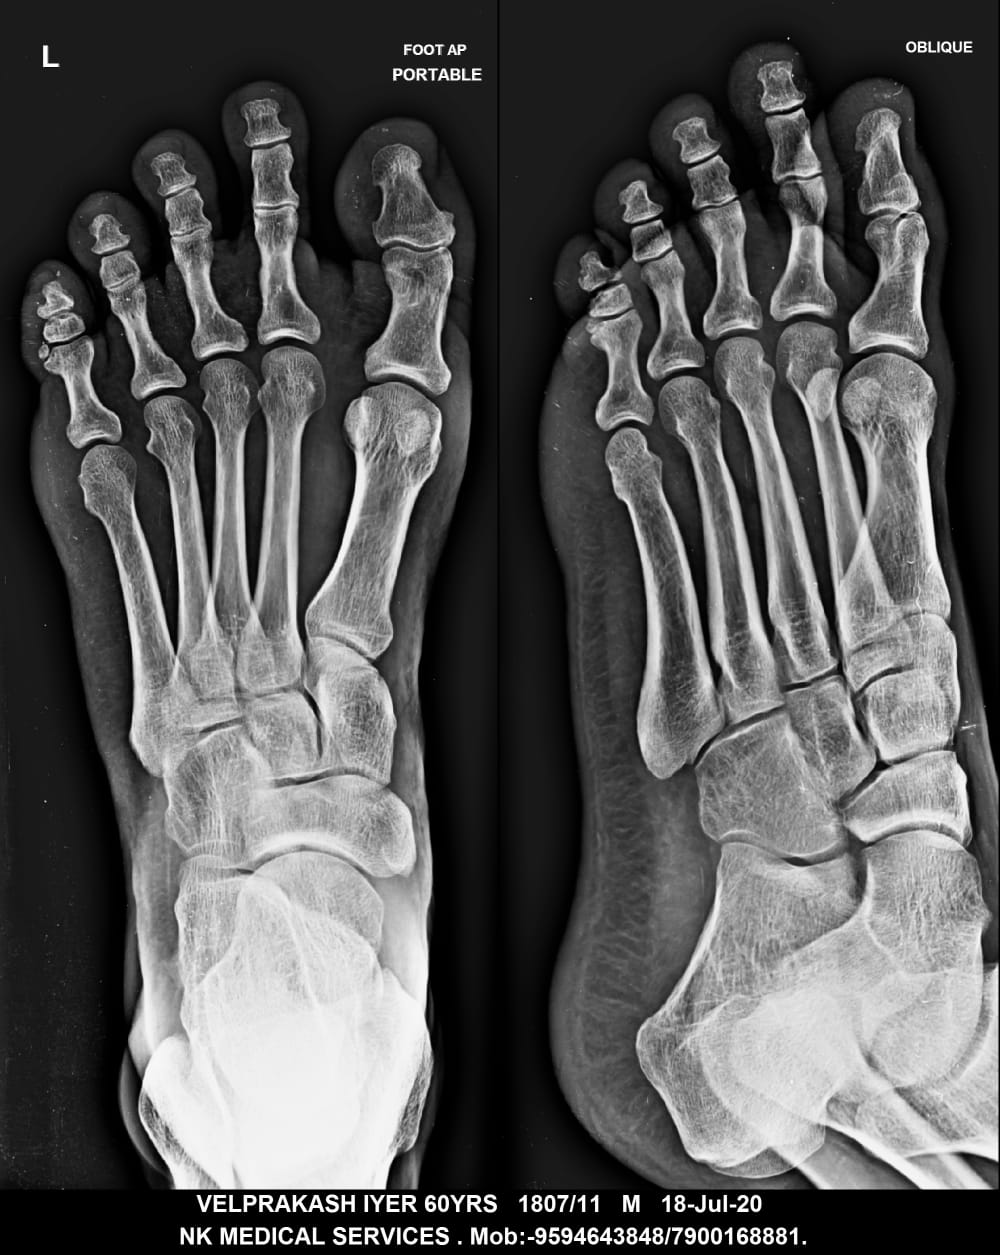

Getwell Urgent Care of Southaven uses digital X-ray technology, which uses less radiation, provides fast turnaround of images, and gives us the ability to manipulate images for more accurate readings. We follow the highest safety standards, with certified equipment and licensed radiology technologists to ensure an excellent image the first time and minimal exposure to radiation. We use digital X-ray to diagnose broken bones, certain lung conditions (e.g., pneumonia), and certain abdominal conditions.